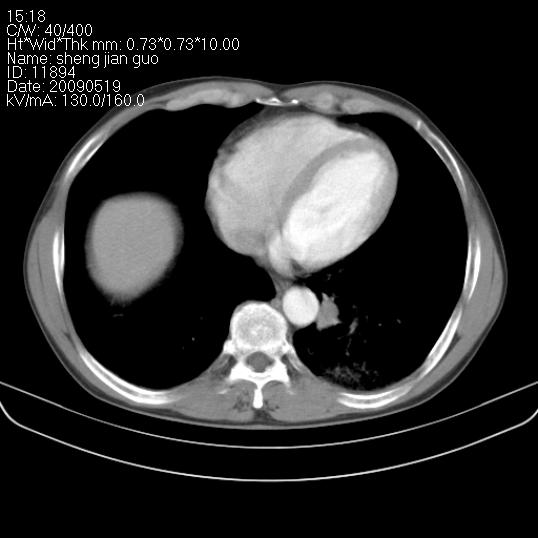

以下是引用zjzjr在2009-5-19 17:25:00的发言:[br]支持楼主考虑,另左肺下叶阻塞性炎症。

以下是引用zhao_bin2008在2009-5-19 17:48:00的发言:[br]支持左肺下叶周围型肺癌并阻塞性肺炎。

以下是引用杀毒软件在2009-5-19 17:36:00的发言:[br]支持楼主

以下是引用zsl6918在2009-5-20 7:10:00的发言:[br]左侧中心型肺癌!